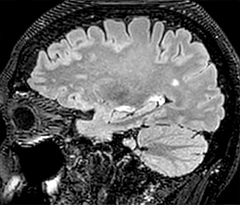

This is an example of acute ischemic stroke with distal occlusion of the right posterior cerebral artery. Note the improved visibility of the ischemic territory on the diffusion weighted image with high b-value. The 3D FLAIR shows a distal PCA occlusion. The fast SWIp depicts the thrombus on the isolated second echo image. The total scan time (including SmartBrain, preparations and a fast 3D T1w TSE Gd) is 8:00 minutes.

Dr. Savatovsky appreciates the improvements and flexibility that Elition with Compressed SENSE and MultiBand SENSE provides, particularly for stroke patients. “For stroke, it allows us to cut about 5 minutes off of our stroke protocol, or to keep the same acquisition time and get more insights.” The ability to perform more sequences can help in making a swift and confident diagnosis. “For example, our stroke cases usually include the regular sequences that every center does (b1000 diffusion, FLAIR, time-of-flight angiography), but we also image supra aortic vessels, and we can replace a gradient echo sequence with a fast 50-second susceptibility-weighted sequence, and all of this doesn’t add much time. because all the regular sequences are accelerated on Elition.” “The time savings with Compressed SENSE and MultiBand SENSE make it easier to add sequences to give us additional insights. Depending on the context and the first results, we might add a DSC perfusion to assess the ischemic penumbra, an ASL perfusion to help find an alternative cause in case of normal diffusion, or add a high-resolution T1 sequence for a stroke patient, to quickly assess wall imaging in emergency cases. The additional sequences can help improve patient management, because we can already consider some alternative diagnoses if the morphological MRI is normal.”

Using MultiBand SENSE allowed the staff to improve their diffusion quality. “Our diffusion sequence was already fast before, about 40 seconds. Now with Elition, it still lasts 40 seconds, but we improved the spatial resolution by 0.2 mm and use high b-values to be more sensitive to visualize changes related to acute stroke,” says Dr. Savatovsky. “We now also developed a high resolution DTI sequence (1.3 x 1.3 x 2 mm) that can be reformatted and takes 2 to 5 minutes depending on the coverage. We use it every time we have a doubt, or when we expect the diffusion to be abnormal but don’t see that on the fast sequence. We occasionally spot small ischemic infarctions that would not have been visible with the regular diffusion sequence.”